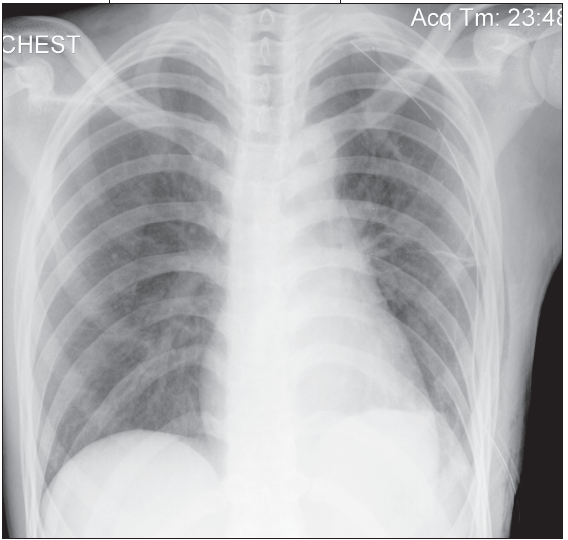

Curt Stankovic, MD; Prashant V. Mahajan, MD, MPH, MBA

A 17-year-old Asian male with no significant medical history presented to the emergency department (ED) with acute shortness of breath and associated left-sided chest pain.

A spontaneous pneumothorax is a collection of air or gas between the visceral and parietal pleura that causes the lung to collapse.